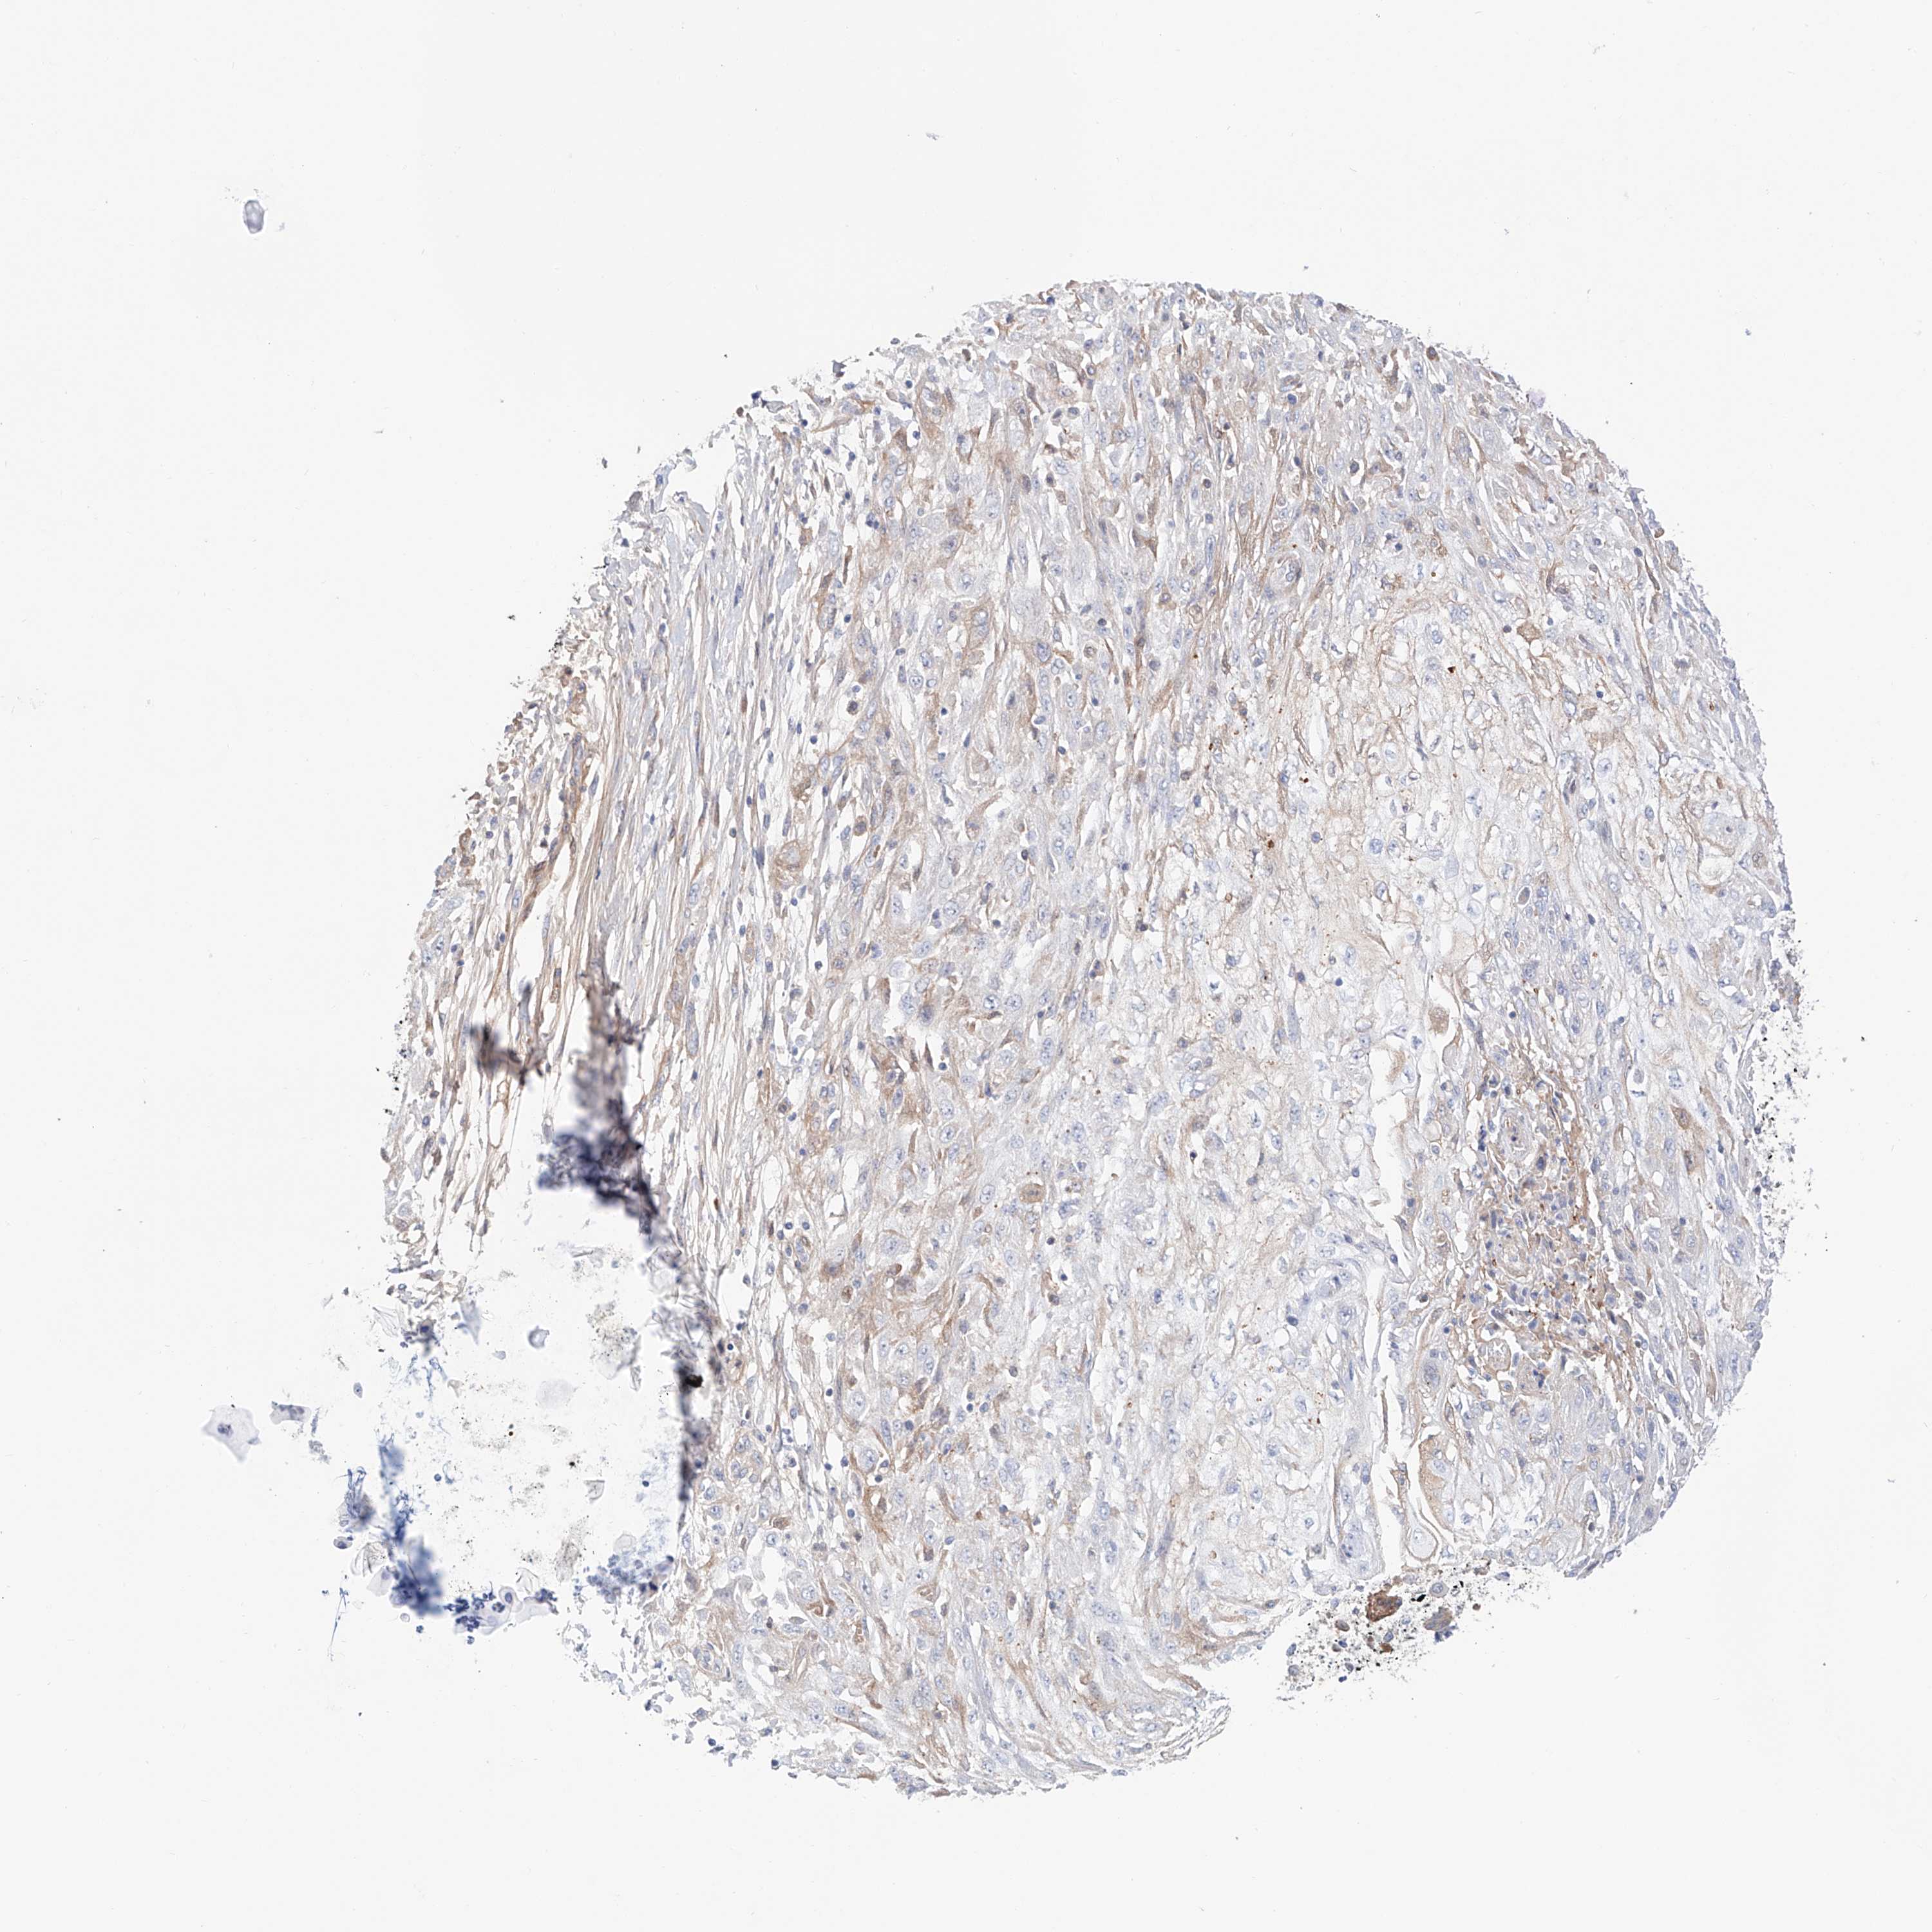

Basal cell and squamous cell cancer

SKIN CANCER - Protein expressioni

A mouse-over function shows sample information and annotation data. Click on an image to view it in a full screen mode. Samples can be filtered based on level of antibody staining by selecting one or several of the following categories: high, medium, low and not detected. The assay and annotation is described here.

Each image is clickable and will lead to virtual microscopy that enables deeper exploration of all samples and also displays staining intensity scores, fraction scores and subcellular localization as well as patient and tissue information for each sample.

Antibody HPA030646

Staining

Medium

Strong

>75%

Location

Cytoplasmic/membranous

Squamous cell carcinoma, NOS